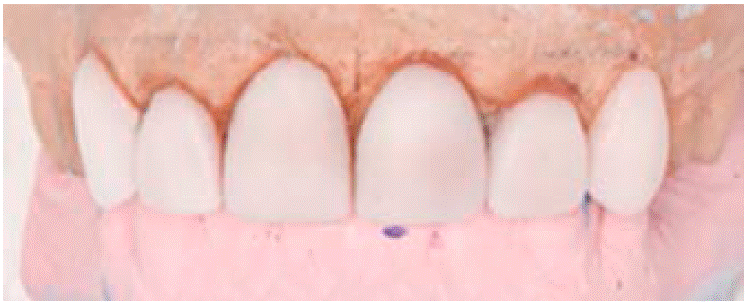

Para valorar los alcances que se pudieran tener en el tratamiento, se realizó un encerado de diagnóstico para recuperar la parte estética y programar la preparación de los dientes 1.3, 1.2 y 2.3 para futuras carillas y provisionalizar a su vez 1.1, 2.1, 2.2 (Figura 3).